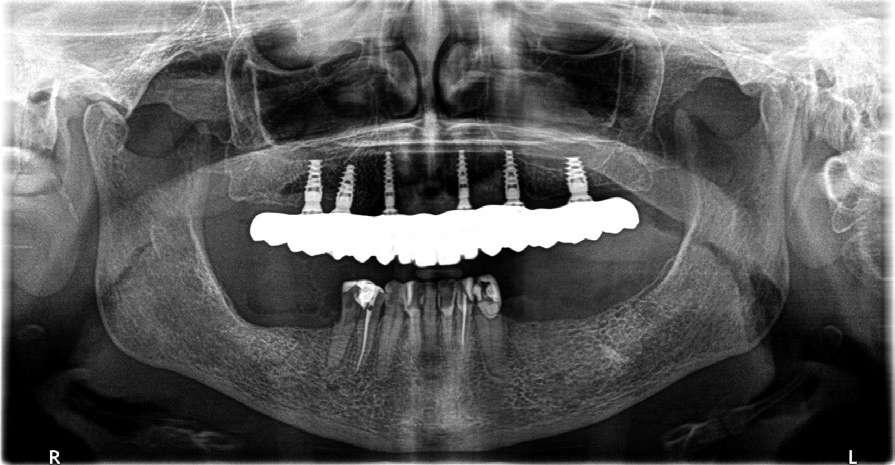

En su motivo de consulta demanda una “solución fija y menos voluminosa“ para rehabilitar su boca. (Fig. 1 y 2).

Guía radiográfica para maxilares edéntulos y planificación virtual de la colocación de los implantes

Para poder planificar la cirugía guiada para la colocación de implantes en pacientes completamente edéntulos, realizamos un duplicado de la prótesis completa modificada rebasada en acrílico transparente, a la que se le añaden entre seis y ocho marcadores de gutapercha esféricos distribuidos uniformemente como elementos fiduciarios para la realización del doble escáner y permitir el ajuste preciso de los dos escaneados en el software DTX Studio™ Implant.

Realizamos un primer escáner radiográfico a la paciente con la guía radiográfica sujeta en la posición correcta en oclusión y un segundo escaneado posicionando la guía radiográfica en una esponja colocándola aproximadamente en la misma orientación

en la que estaba posicionada para el escaneado del paciente.

Posteriormente, exportamos los datos como archivos DICOM.

Mediante el software DTX, superponemos estos archivos junto con el STL del encerado ideal.

La paciente presentaba una Clase III de Cawood y Howell con una cresta alveolar con adecuada anchura y altura por lo que planificamos la colocación de seis implantes. No consideramos necesario añadir más implantes a nuestra planificación puesto que se trataba de una arcada cuadrada con un mínimo cantilever anterior. Además, se planificaron tres tornillos de anclaje para proporcionar una seguridad adicional. Diseñamos una férula quirúrgica para un procedimiento de fresado piloto guiado que guía la fresa espiral de 1,5 y 2,0 mm.

Seleccionamos implantes NobelActive® con cambio de plataforma integrado que desplaza el micro gap hacia dentro en sentido horizontal, alejando las filtraciones bacterianas del hueso y una conexión cónica que proporciona estabilidad a la unión de implante pilar. Además, gracias a las herramientas de planificación del software podemos predecir de antemano qué pilares intermedios vamos a necesitar. (Fig. 6, 7 y 8).